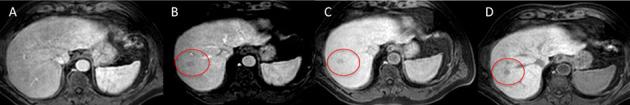

On computed tomography (CT) and magnetic resonance imaging (MRI), hepatocellular tumors are characterized based on typical imaging findings. However, hepatocellular adenoma, focal nodular hyperplasia, and hepatocellular carcinoma can show uncommon appearances at CT and MRI, which may lead to diagnostic challenges. When assessing focal hepatic lesions, radiologists need to be aware of these atypical imaging findings to avoid misdiagnoses that can alter the management plan. The purpose of this review is to illustrate a variety of pitfalls and atypical features of hepatocellular tumors that can lead to misinterpretations providing specific clues to the correct diagnoses.

在计算机断层扫描(CT)和磁共振成像(MRI)上,根据典型的影像学表现可对肝细胞肿瘤进行特征描述。然而,肝细胞腺瘤、局灶性结节性增生和肝细胞癌在 CT 和 MRI 上可能会出现不常见的表现,这可能导致诊断上的挑战。在评估局灶性肝病变时,放射科医生需要注意这些非典型的影像学表现,以避免误诊,误诊可能会改变治疗计划。本文旨在说明导致误诊的肝细胞肿瘤的各种陷阱和非典型特征,并提供正确诊断的具体线索。